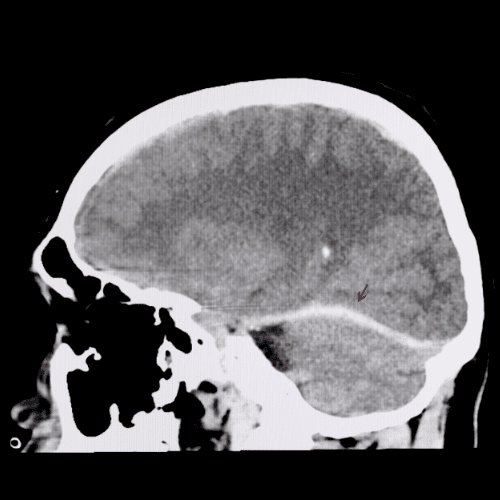

- Serious head trauma

- Neck/brain/back injury

Overall, these kinds of injuries are well-defined as those that create severe damages to your back, brain, head, or spine, including fractures, which may lead to severe or long-lasting incapacity. These kinds of injuries typically happen from severe accidents or trauma.